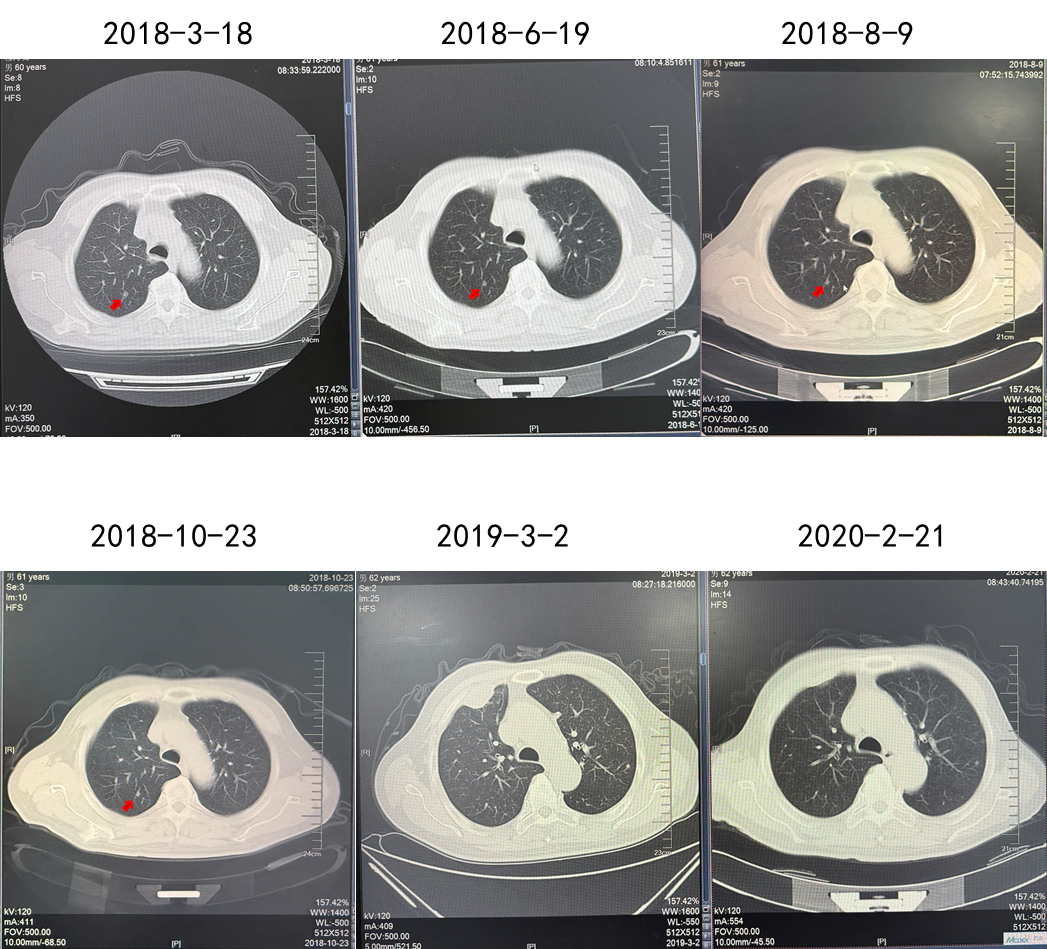

2018.03 PET-CT提示多发肺转移,肋骨转移

2018.03.22胸壁穿刺显示转移性癌,考虑肾来源

诊断为T2N0M1,IV期,IMDC低危

2018.03.22舒尼替尼50 mg QD。肋骨肿瘤注射唑来膦酸3周1次(共3次),同步放疗3 Gy(共10次)。

疗效:肋骨病灶疾病稳定(2年),肺部病灶部分缓解(2年)。

(舒尼替尼单药联合放疗,肋骨病灶实现SD)

(舒尼替尼单药联合放疗,肺转移病灶实现PR)

该例患者诊断为左肾透明细胞癌,T2N0M0,术后5.5年复发,伴肋骨转移、肺转移和胸壁转移。结合循证医学证据及中国临床肿瘤学会(CSCO)肾癌诊疗指南对低危患者推荐,优先使用舒尼替尼进行一线治疗,患者出现不耐受情况,调整剂量后肺部病灶获得部分缓解,肋骨病灶疾病稳定,PFS 2年。后续进展可考虑其他治疗方案。